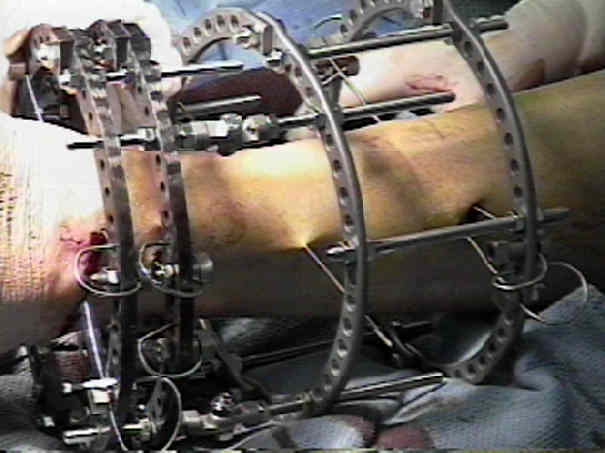

Аппарат Илизарова: принцип работы и применение